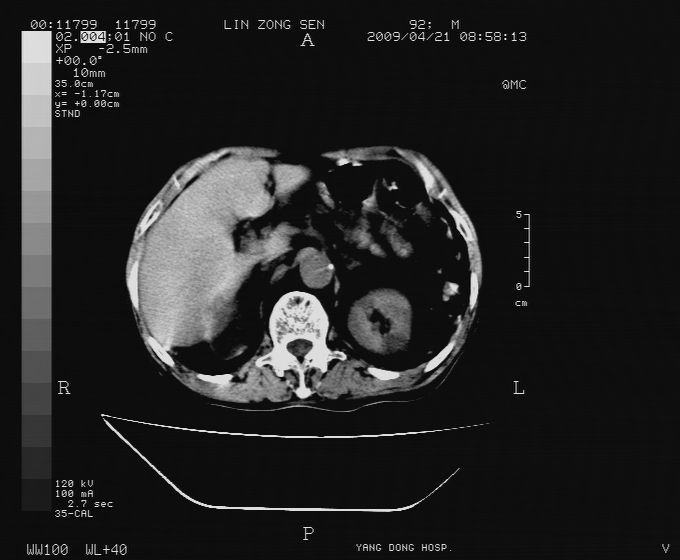

以下是引用卜一在2009-4-22 4:08:00的发言:[br]右肾积水伴输尿管上段积水!左侧肾多发囊肿!左侧腹壁软组织增厚,层次模糊,内密度较高—不排除血管瘤伴出血!